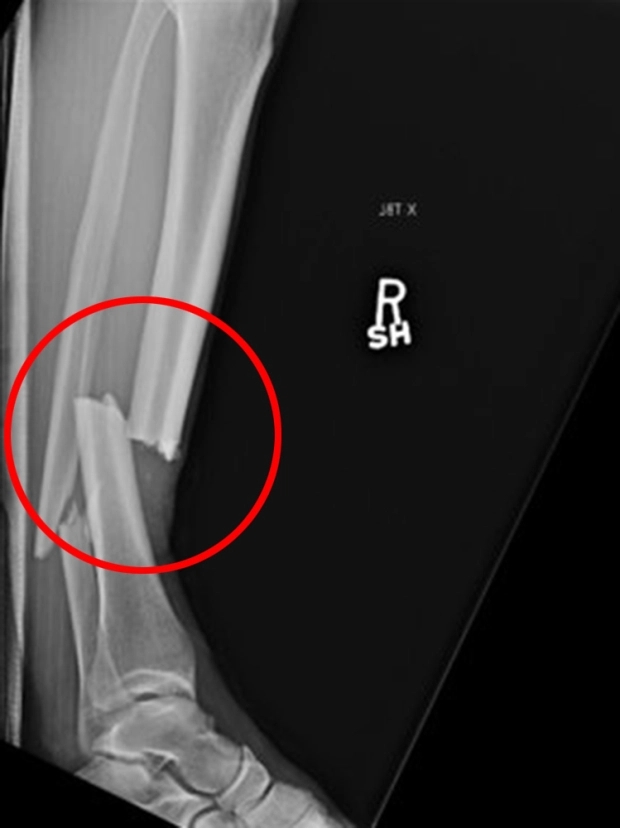

아직도 로우킥끼리 닿아서 한쪽 다리뼈 뒤로 반 넘어간게 잊혀지지가 않는다...

크리스 와이드먼 골절 그건가 | 25.12.23 15:58 | | |